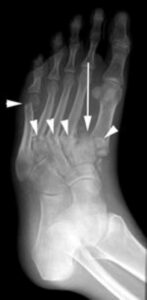

The patient shown in the X-ray had noticed swelling of the foot for approximately 3 weeks without any known injury. The X-ray shows several fractures (arrowheads) and a dislocation of the first metatarsal (arrow). Such a severe injury in patients without diabetes would be seen only after a high-energy trauma.